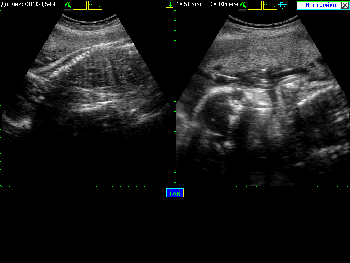

Примеры того, как выглядит экран при различных режимах сканирования можно увидеть в Таблице 4.

Таблица 4. Общий вид экрана в различных режимах сканирования.

Вид экрана Режим сканирования

Режим сканирования B Режим В

Режим сканирования B+B Режим В+В

Режим сканирования B+M Режим В+М